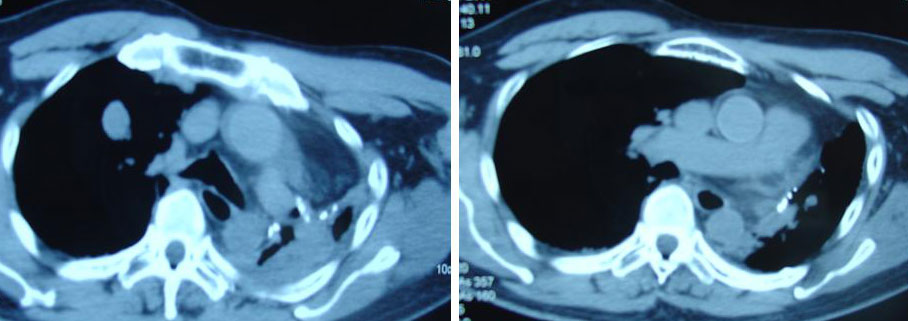

A CT scan of the chest indicated both lungs were studded with numerous nodular lesions of varying sizes measuring 5 mm to 25 mm. A dominant 3 cm nodule was seen in the right lower lobe. There were also multiple small mediastinal lymphadenopathies in the aorto-pulmonary window and pre-aortic region. In short, the CT scan revealed An Tee had extensive lung nodules in both her lungs that had also spread to the adjacent lymph nodes.